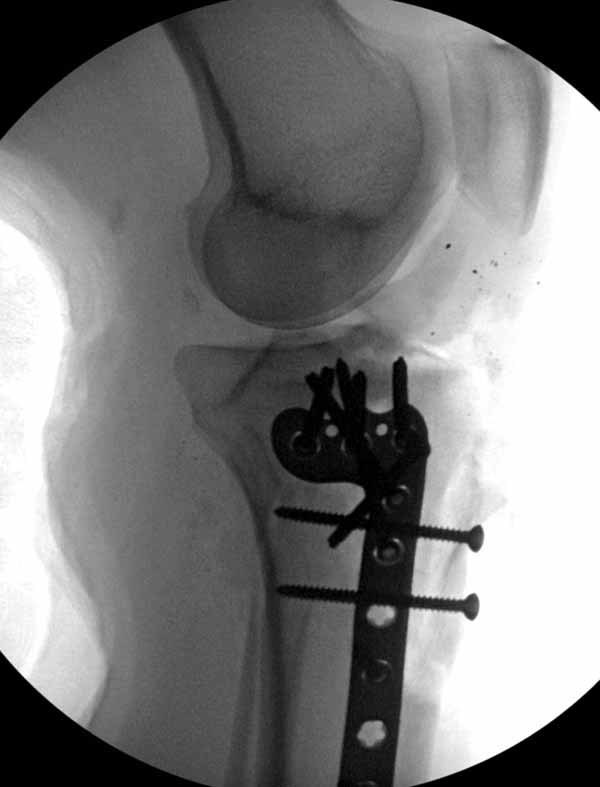

Клиника и течение заболевания похожи на однокамерную кисту. Больная молодая, желательно сохранить собственную головку. Надо спешить с операцией, иначе скоро произойдет перелом через тонкую стенку. Во время операции внутри будет пустота и небольшое количество жидкой крови.

Из всех перечисленных методов подходит вариант пластики аутокостью и усиление (арматура) шурупами. Основная задача сохранить интактную медиальную стенку и латеральный кортекс. Доступ передне-латеральный, но надо работать спереди шейки через небольшое окно в 10-15 мм. Фиксацию надо проводить между медиальной тонкой стенкой головки и латеральным кортексом. Каннюлированные шурупы 6.5 мм очень грубые и могут разрушить остаток стенки. Фиксировать надо кортикальными шурупами 3.5 мм, которые создадут мостик и арматуру в шейке. Провести по периметру шейки 4, и в центре пару шурупов. Во время операции и при манипуляции соблюдать осторожность, в любой момент может наступить стресс перелом. Заранее надо заказывать длинные шурупы!